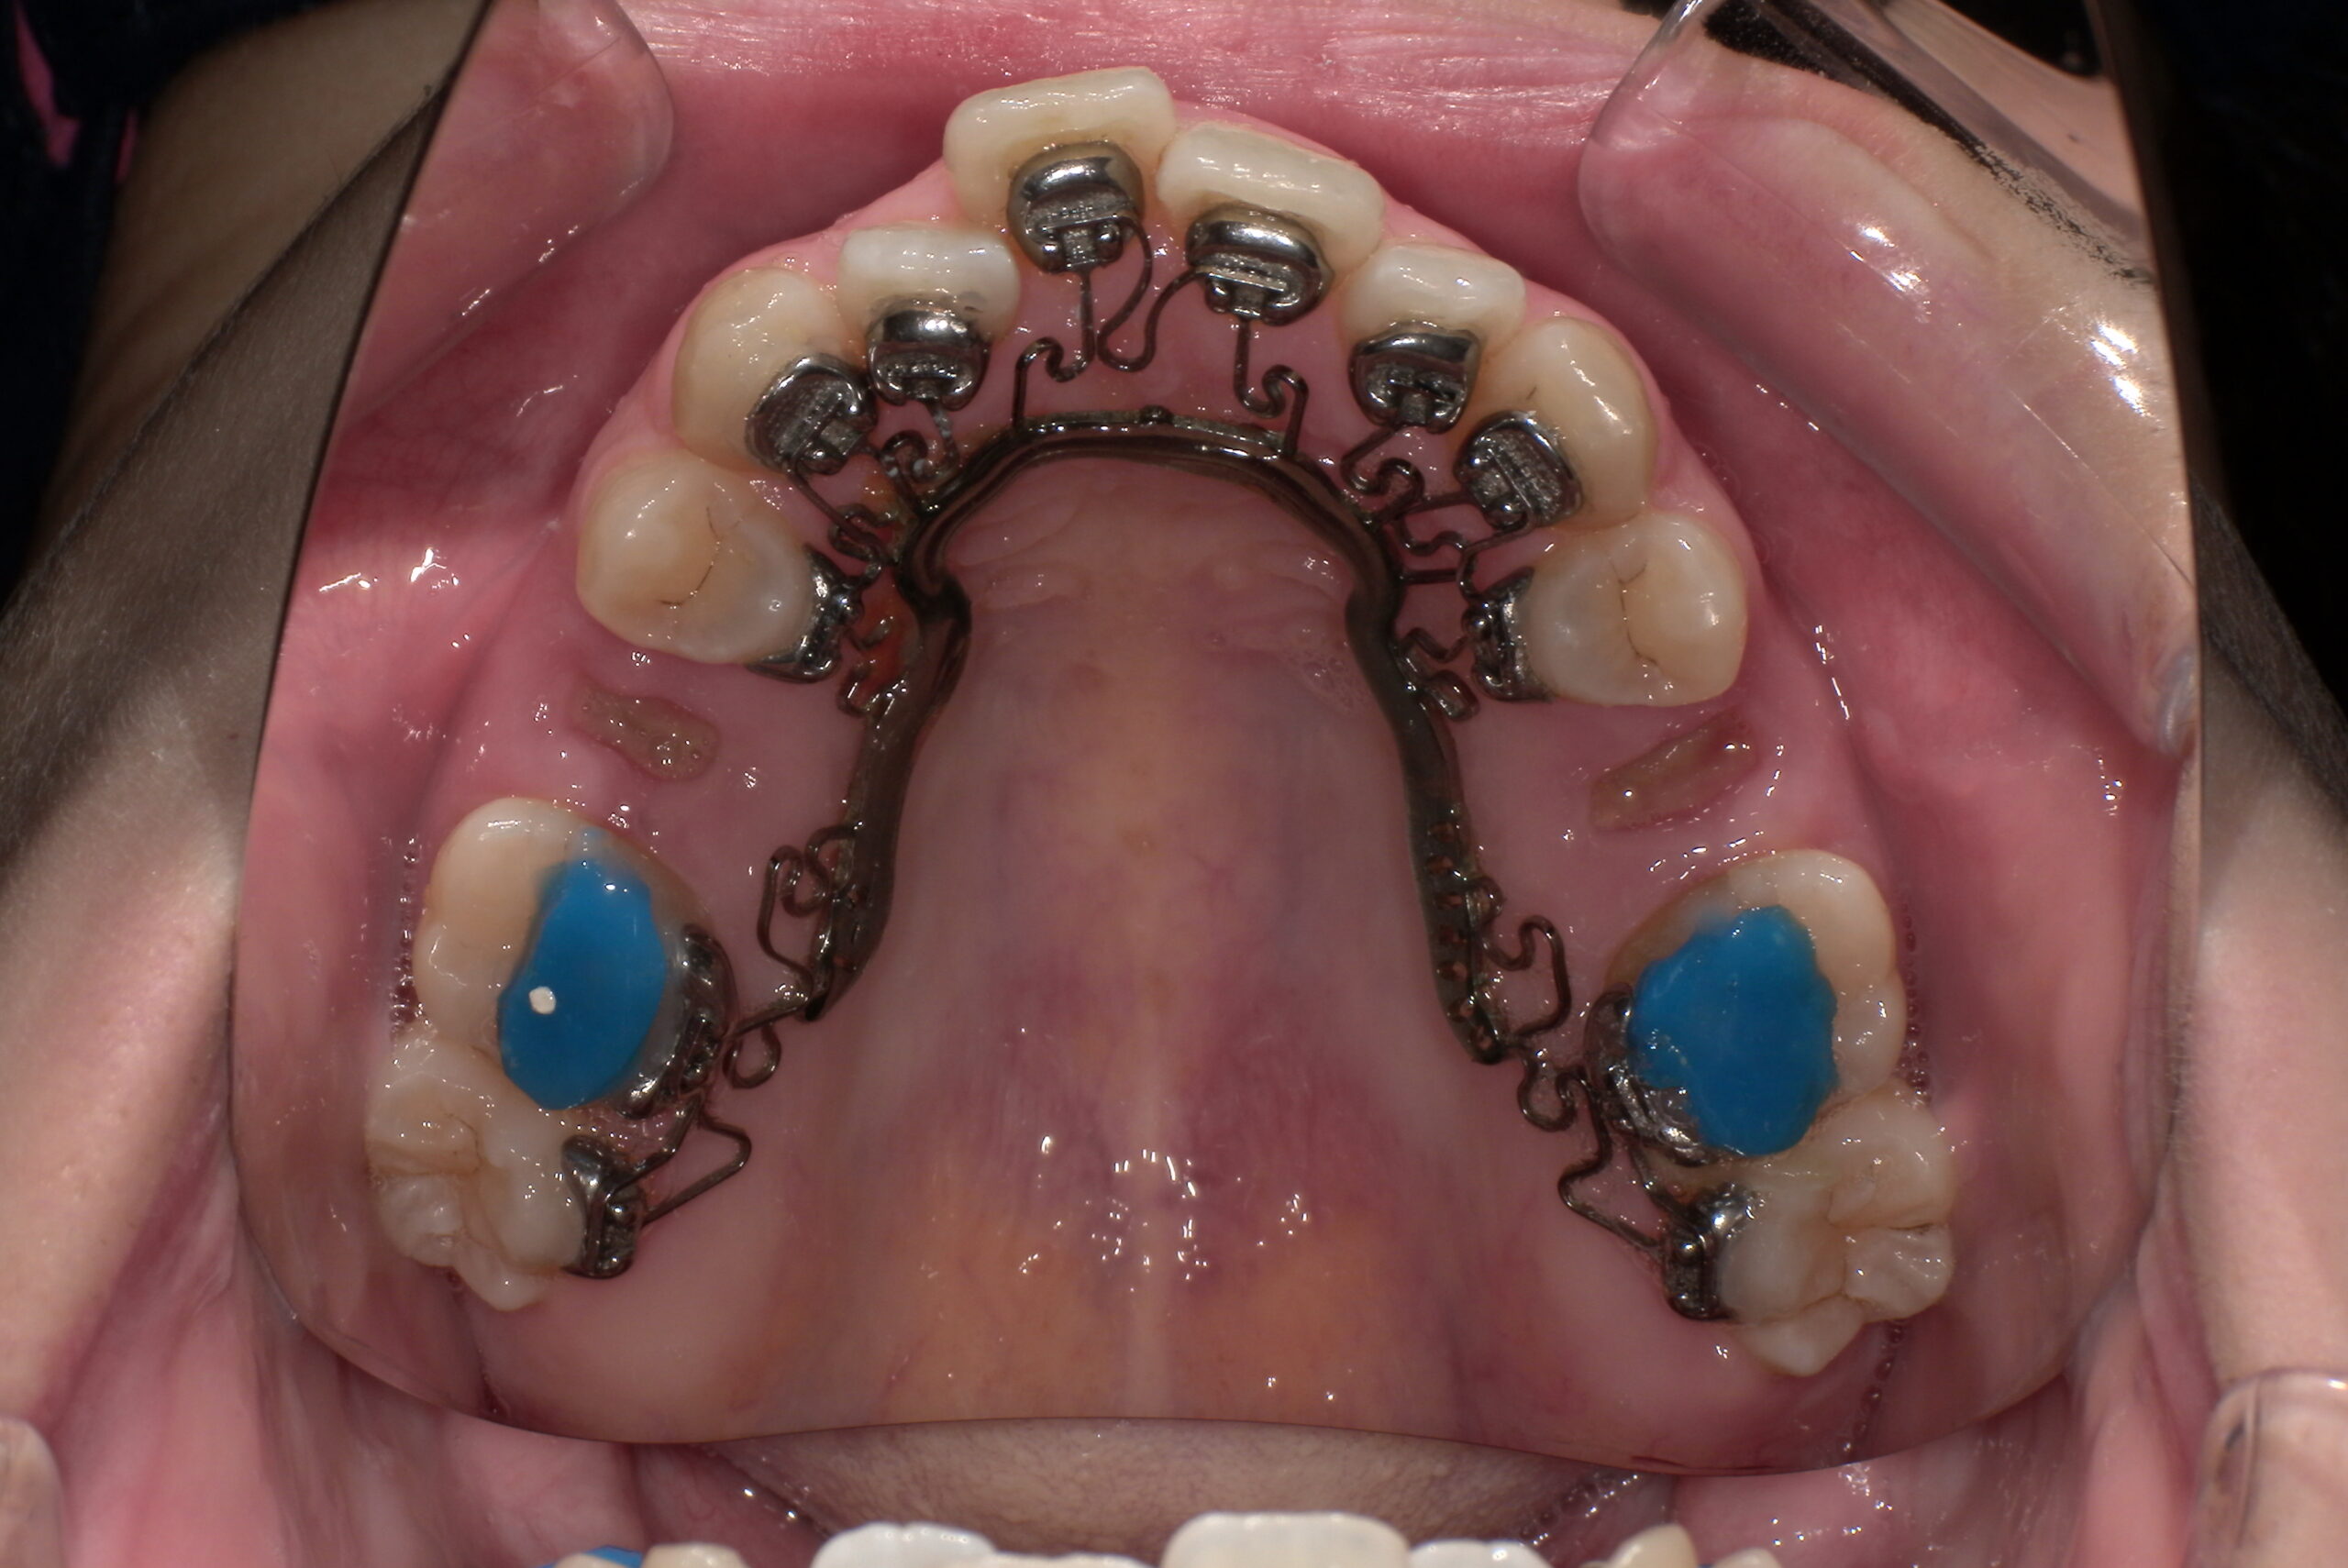

上顎

(青い材料は下の歯が上の装置にぶつからないよう、咬み合わせを一時的に上げる材料です)